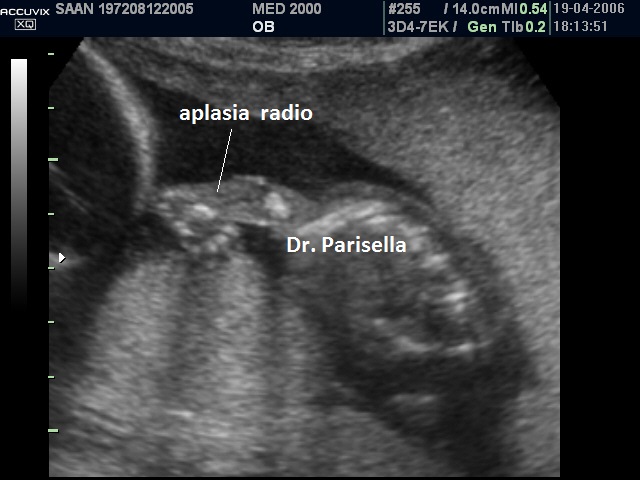

aplasia radio

L) anomalie arti (Limbs): aplasia radio, fusione radio ulna, polidattilia

5) anomalie degli arti (aplasia del radio).